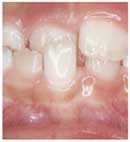

交叉咬合で歯肉が下がった例

反対咬合の時と同じように、かみ合わせが逆になっている部分の下の前歯は、ダメージを受けやすくなります。(歯肉が下がったり、歯がぐらぐらしたりします)